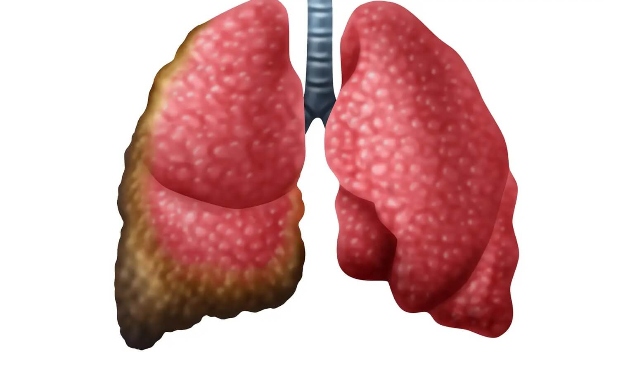

El mesotelioma es un cáncer raro que se desarrolla en las membranas delgadas que recubren el tórax y el abdomen, más comúnmente causado por la inhalación de fibras de asbesto. Estas fibras a menudo se encuentran en aislamientos, baldosas de vinilo, materiales para techos y pinturas.

Normalmente, el mesotelioma presenta un número bajo de mutaciones genéticas puntuales únicas, lo que lo hace de difícil detección a través de los tradicionales análisis de sangre. Sin embargo, la presencia de rearreglos cromosómicos — como si se tratara de palabras desordenadas en una oración — ofrece un nuevo blanco de diagnóstico. Eso difiere de muchos otros tipos de cáncer que a menudo dependen de la detección de mutaciones puntuales únicas — pequeños cambios en la secuencia de ADN, similar a la alteración de una sola letra en una palabra.